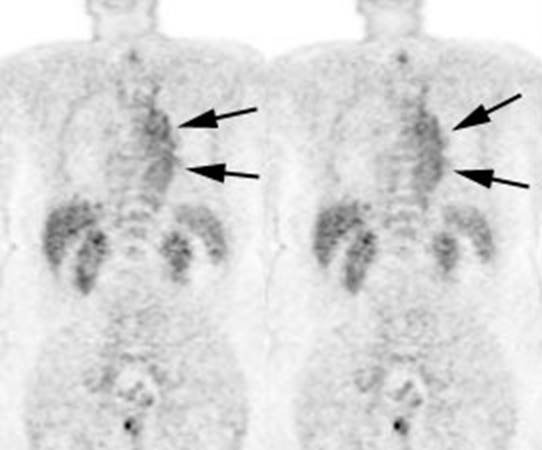

Figure 21 - Marrow activity: The images below are from

two separate patients each showing mild FDG accumulation within the vertebral

bodies.

Figure 22 - Growth colony effect: The patient shown below

had received growth colony stimulating factor (GCSF). Note the extensive

increased marrow activity. Note increased splenic activity also seen as a result of GCSF therapy.